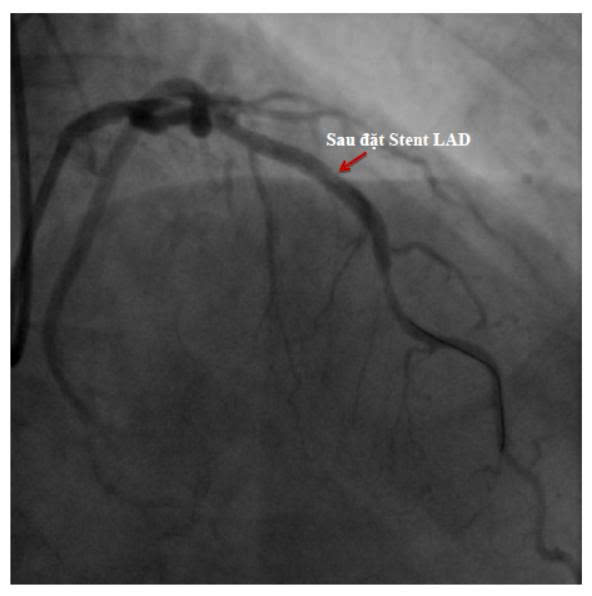

👉 Với trường hợp này, đặt stent mạch vành kịp thời đã giúp tái thông dòng máu, giảm nguy cơ nhồi máu cơ tim và bảo vệ chức năng tim lâu dài.

- Là thủ thuật đưa một khung kim loại nhỏ (stent) vào vị trí mạch bị hẹp

- Giúp giữ lòng mạch luôn mở, máu lưu thông nuôi tim tốt hơn

- Ít xâm lấn – thời gian hồi phục nhanh – hiệu quả cao nếu làm đúng chỉ định